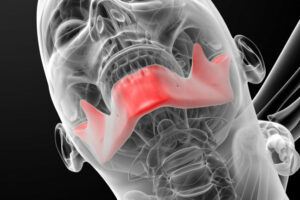

Cleft Lip and Palate

During early pregnancy, separate areas of the face develop individually and then join together, including the left and right sides of the roof of the mouth and lips. However, if some parts do not join properly, sections don't meet and…